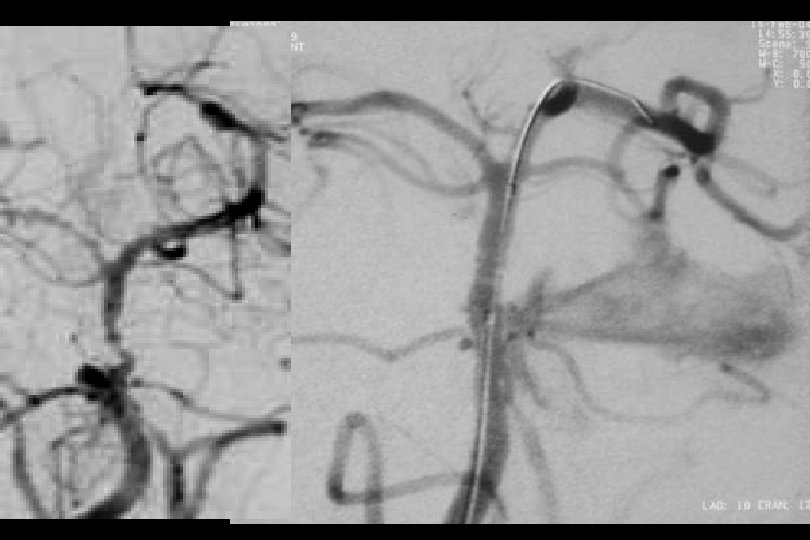

71 y kadın hasta En iyi medikal tedavi altında post fossa iskemik ataklara neden olan baziler stenoz

Sağ brakial yaklaşım ile Reflex /Navien servikal R- VA’e ve intrakraniyal segmente ilerletilmiştir.

• • • Distal Giriş Kateterleri Exchange in minumuma indirilmesi (primer gateway le bypass veya Reflex ve monorail balonla bypass pta balon Mikrokateterden bırakılan stent kullanılması

PTA sonrası

. . 6 mm Solitaire ile Stentleme sonrası

66 mm Solitaire ile post stent

Post stent